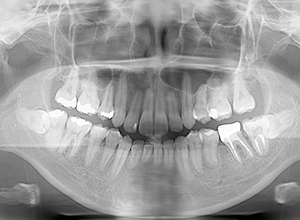

X-Ray

X-Ray所見

セファロ所見 下顎骨体部は小さくないものの下顎枝は短く、下顎頭は後方に位置付き中顔面高は高いため、下顎はクロックワイズローテーションしており、前後的にはII級の骨格形態を示していた。

パノラマ所見 上下顎両側第三大臼歯は埋伏していた。下顎右側大臼歯から犬歯まで近心傾斜し、左側においては左下5を境に大臼歯は近心傾斜、近心の歯は遠心方向へ傾斜が認められた。